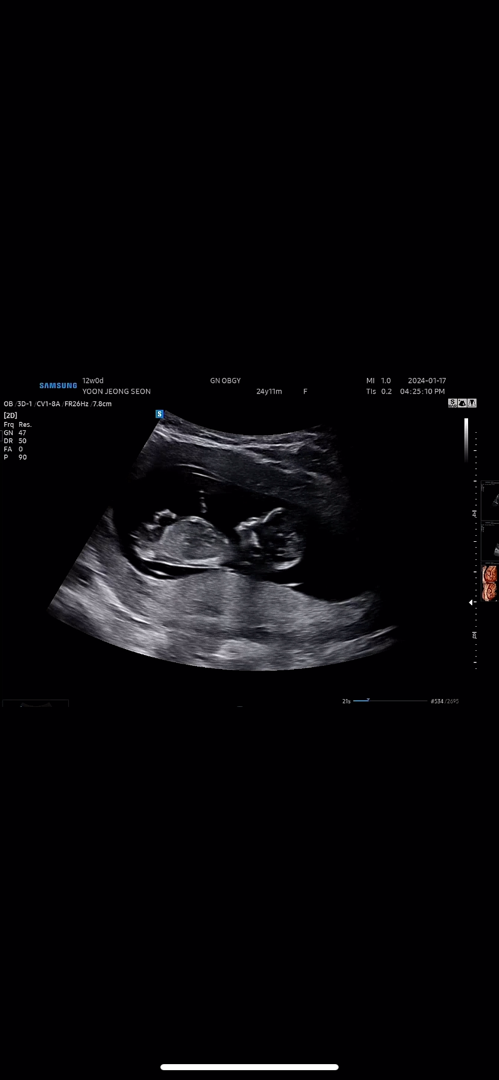

12주 초음파 각도법 한번씩 봐주세용 ! ㅠ

12주차되서 초음파보구왔어여 ! 각도법으로 한번씩 성별봐주세여 ㅠ 전 봐도 모르겟네용 ㅠㅠ